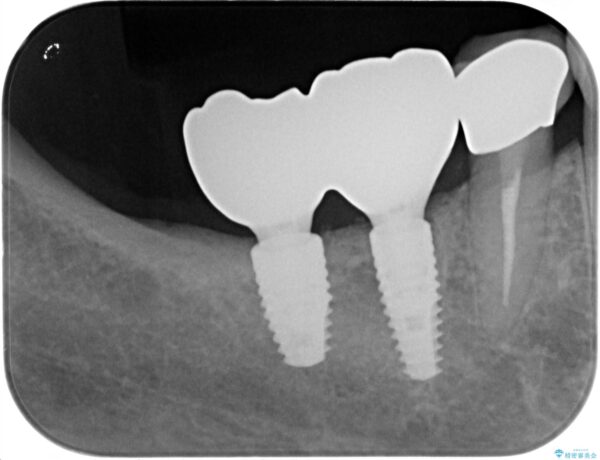

奥歯から膿のにおいがする インプラントによる機能回復 治療前画像 奥歯から膿のにおいがする インプラントによる機能回復 治療前画像 奥歯から膿のにおいがする インプラントによる機能回復 治療前画像 奥歯から膿のにおいがする インプラントによる機能回復 治療前画像 奥歯から膿のにおいがする インプラントによる機能回復 治療前画像 奥歯から膿のにおいがする インプラントによる機能回復 治療前画像

治療中

奥歯から膿のにおいがする インプラントによる機能回復 治療中画像 奥歯から膿のにおいがする インプラントによる機能回復 治療中画像 奥歯から膿のにおいがする インプラントによる機能回復 治療中画像 奥歯から膿のにおいがする インプラントによる機能回復 治療中画像

治療後

奥歯から膿のにおいがする インプラントによる機能回復 治療後画像 奥歯から膿のにおいがする インプラントによる機能回復 治療後画像 奥歯から膿のにおいがする インプラントによる機能回復 治療後画像 奥歯から膿のにおいがする インプラントによる機能回復 治療後画像